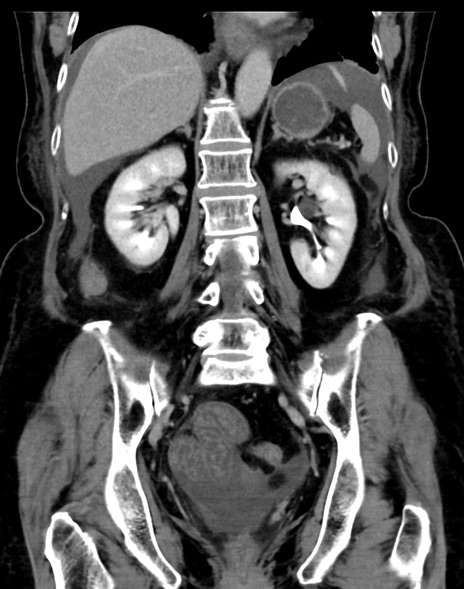

症例13 CT(冠状断像)1日半後